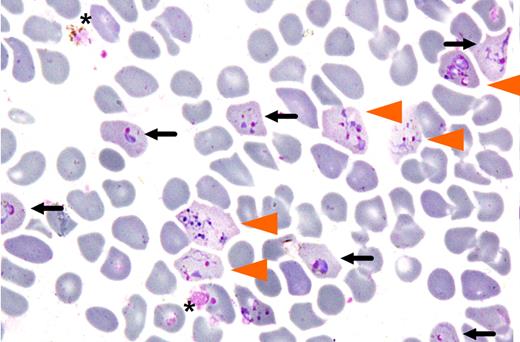

Invasion of enrinched reticulocyte population by Plasmodium vivax. Cells invaded by either one (black arrow) or multiple merozoites (orange arrowhead) after 24 hours of in vitro culture are shown (from Figure 5 of Russell et al1 ).

Based on the knowledge that the P vivax merozoite has a strong preference for reticulocytes, the present study outlines a standardized protocol for routine culturing of P vivax. This ex vivo experimental system makes use of reticulocytes isolated from cord blood to induce invasion. Russell and colleagues achieved invasion by this means with parasites derived from 85 patients (see figure). While the re-ported assay system is a notable advance, it still has a number of drawbacks; these include the necessity to perform invasion assays with freshly isolated infected blood samples, and the variable efficiency of the resulting invasion. One may anticipate that further optimization of the experimental system will overcome these deficiencies.